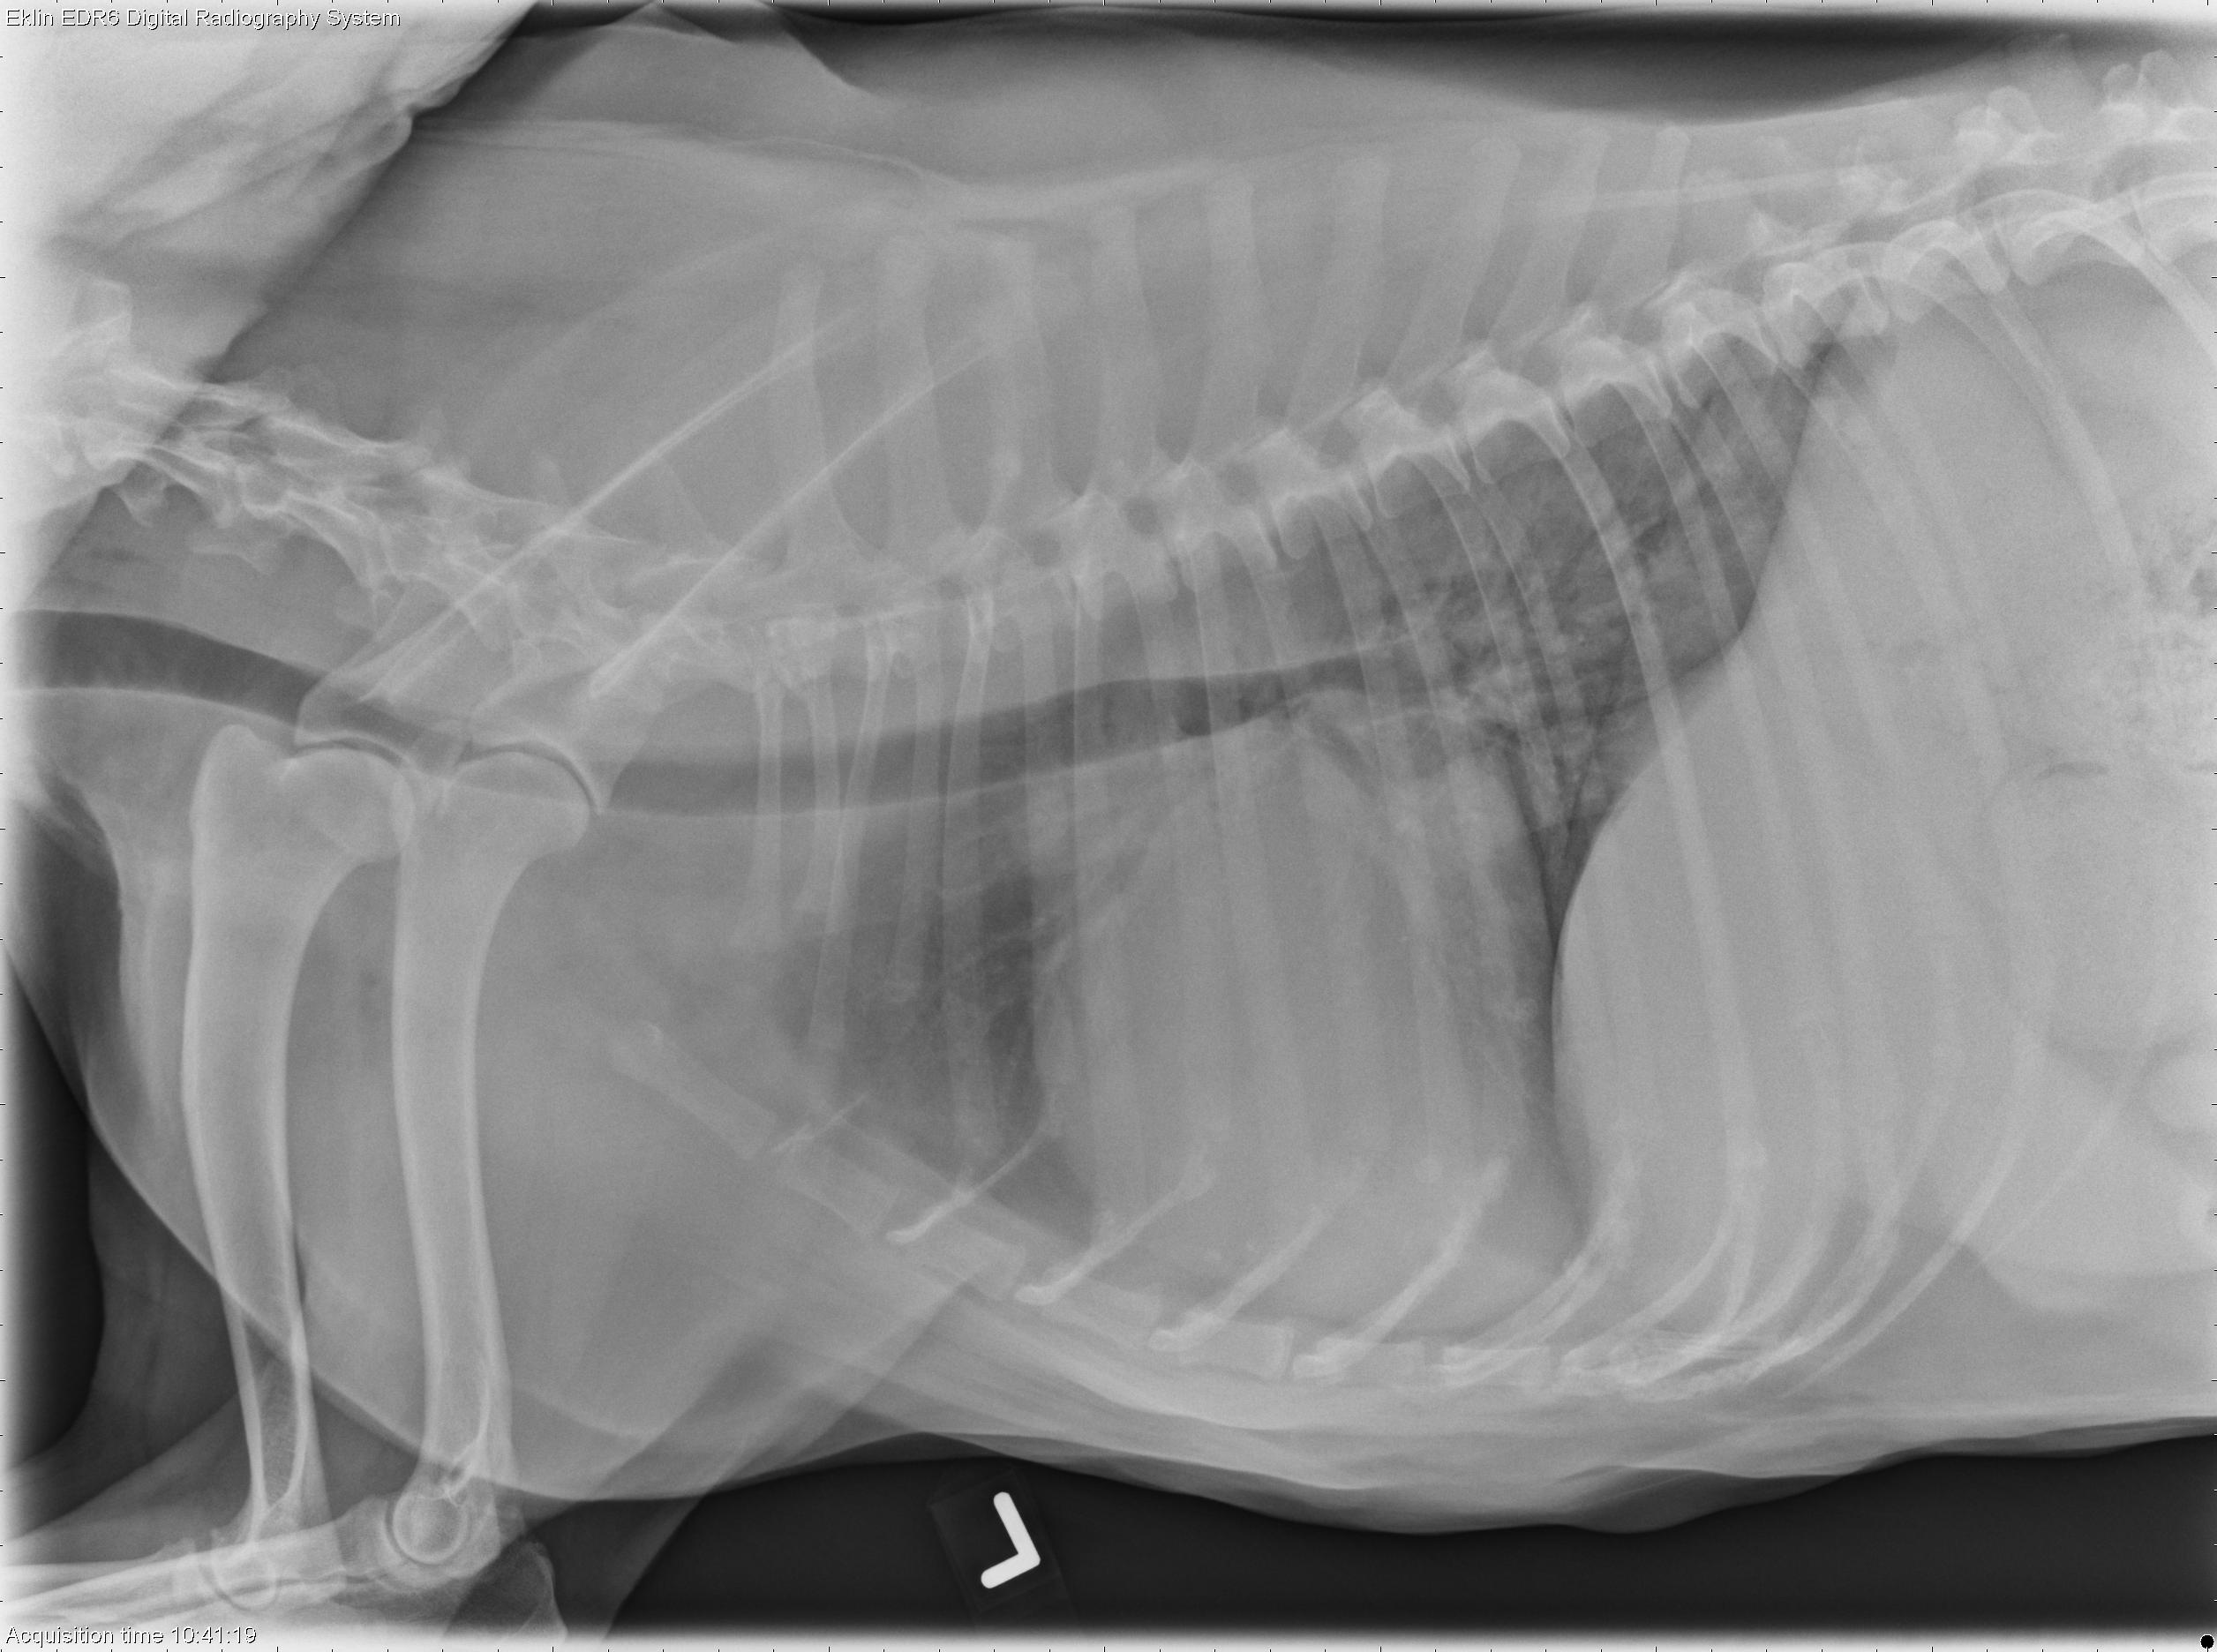

This week’s case is a 16-year-old Australian Cattle Dog with episodes of collapse. What are your differential diagnoses?

R LAT Thorax

The cardiac silhouette is enlarged, with marked left atrial enlargement. The trachea is elevated parallel to the spine, and there is a straightening of the caudal cardiac margin. The pulmonary vasculature is normal in size. There is a fine interstitial pulmonary pattern throughout the lungs, most concentrated in the caudal lung lobes. No pleural effusion is evident. ECG pads are visible on the left and right body wall, causing round opacities superimposed over the heart on the lateral projections. In the portion of the abdomen included, the liver extends beyond the costal arch. The caudal vena cava is normal in size, and the peritoneal detail is normal.

• Cardiomegaly and left heart failure, likely secondary to valvular degeneration

• Hepatomegaly may be due to congestion, metabolic, inflammatory, toxic, or infiltrative disease.

• Severe decompensated myxomatous mitral valve degeneration and mitral valve chordae tendineae rupture

• Pulmonary hypertension and pulmonary fibrosis secondary to left heart failure